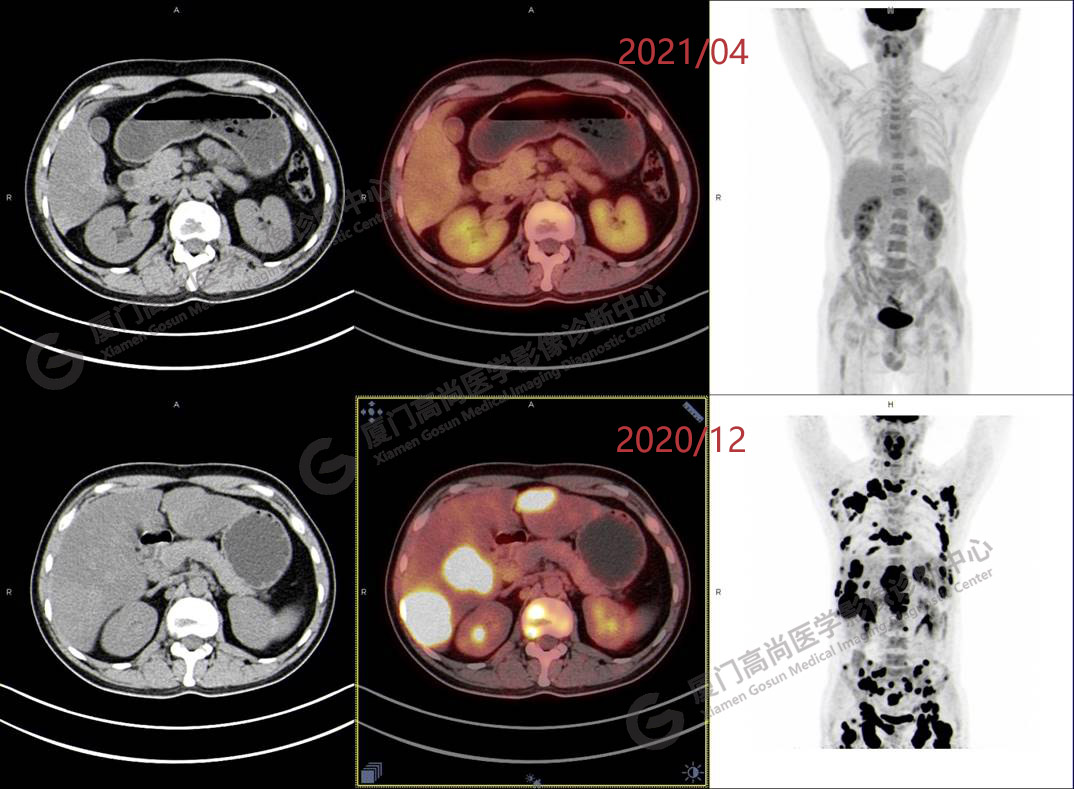

2020.12月本中心PET/CT示:全身多發(fā)腫大淋巴結(jié),代謝不同程度增高;肝臟多發(fā)稍高密度結(jié)節(jié)、脾臟多發(fā)稍低密度結(jié)節(jié),代謝異常增高;全身多發(fā)骨骼溶骨性骨質(zhì)破壞,代謝異常增高,胸2、腰1椎體病理性骨折,診斷為淋巴瘤。隨后,病理確診為彌漫大B細胞淋巴瘤。

患者化療4個療程后,于2021.04月返我中心復查,現(xiàn)患者本人已能自主行走,此次更是獨自一人來我中心復查PET/CT。檢查結(jié)果顯示:原全身多發(fā)病灶基本消失,且病灶代謝基本恢復正常。以下是患者PET/CT前后對比圖像:

PET/CT前后對比圖像2